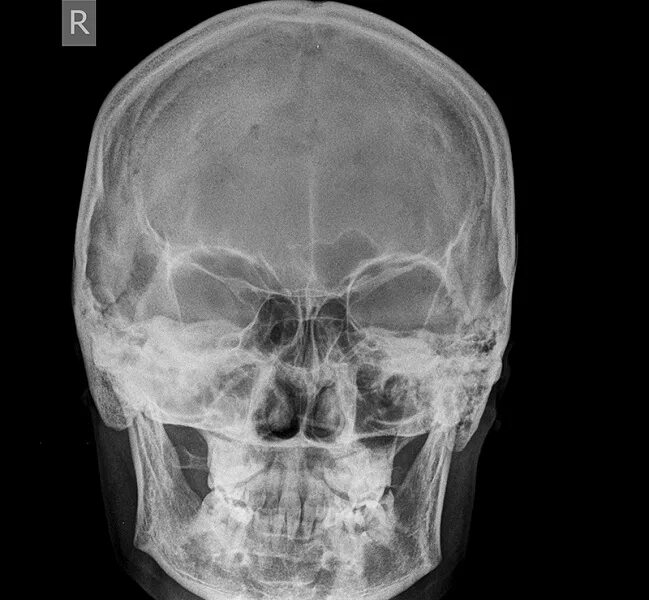

Проекции рентгенограмм черепа